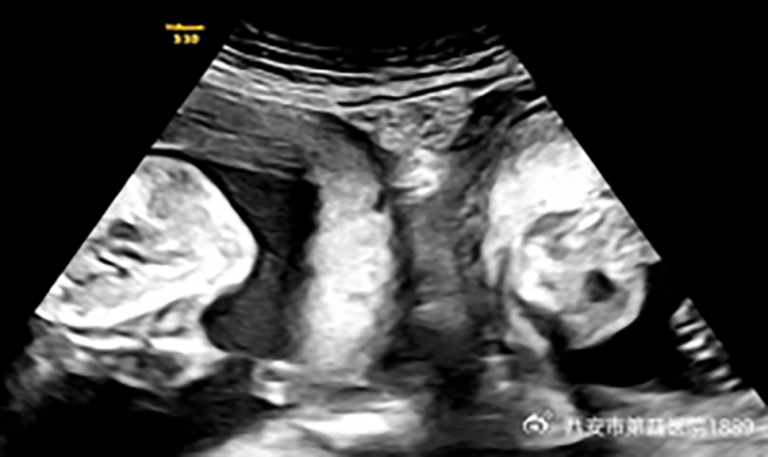

A woman with the rare condition of two uteruses delivered twins, one from each womb, last month at a hospital in northwestern China, according to health officials and state media.

According to the hospital, the new mother was born with two cervixes and two uteruses, a condition called uterine didelphys found in about 1 in 2,000 women.

But in January, Li became pregnant again and discovered during an early ultrasound that she was expecting not just one child but twins – one in each womb.